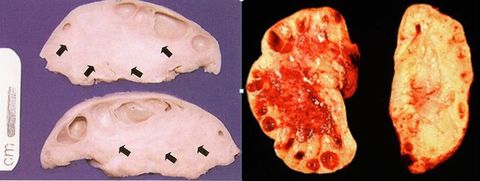

DIAGNÓSTICO. Qual é a etiologia dessa alteração? Leiomioma intramural. Mutação monoclonal.

DIAGNÓSTICO (seta). Quais fases da vida da mulher é mais prevalente? Por quê? Leiomioma subseroso. Gravidez pois é hormônio dependente.

Leiomioma subseroso.

Qual deles é mais sintomático? Submucoso. Produz sangramento facilmente.